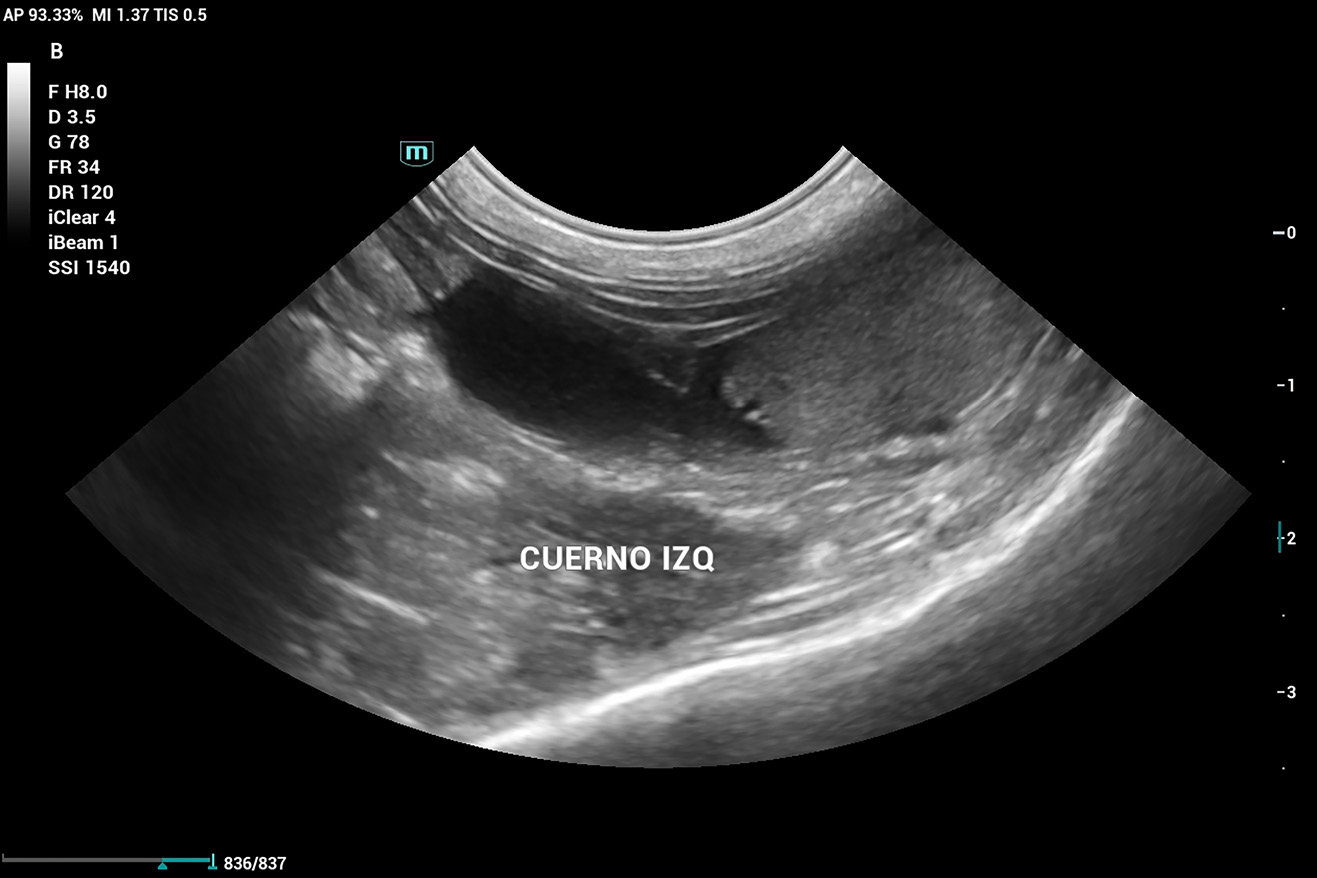

Se realiza ecografía abdominal, que evidencia que aún cuenta con cuernos uterinos (imagen 6), lo que confirma la ovariectomía (no ovariohisterectomía). Por este motivo, se decide enviar una muestra de plasma sanguíneo a un laboratorio externo para evaluar los niveles de 17β-estradiol, dado que en ecografía no se logra distinguir con claridad un remanente ovárico.